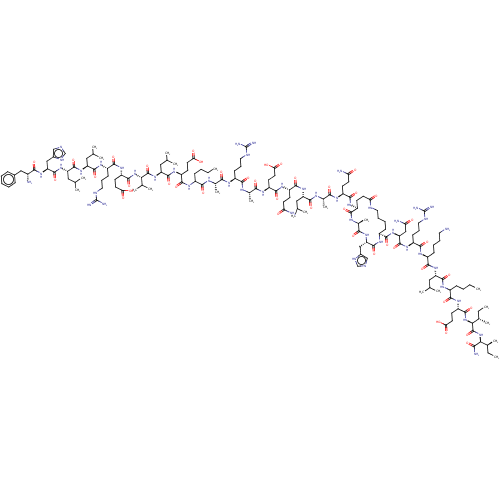

TargetCorticotropin-releasing factor receptor 1(Homo sapiens (Human))

Dupont Pharmaceuticals

Curated by ChEMBL

Dupont Pharmaceuticals

Curated by ChEMBL

Affinity DataEC50: 0.220nMAssay Description:Activity of peptidic agonists on corticotropin releasing factor receptor receptor using agonist-stimulated adenylate cyclase assayMore data for this Ligand-Target Pair